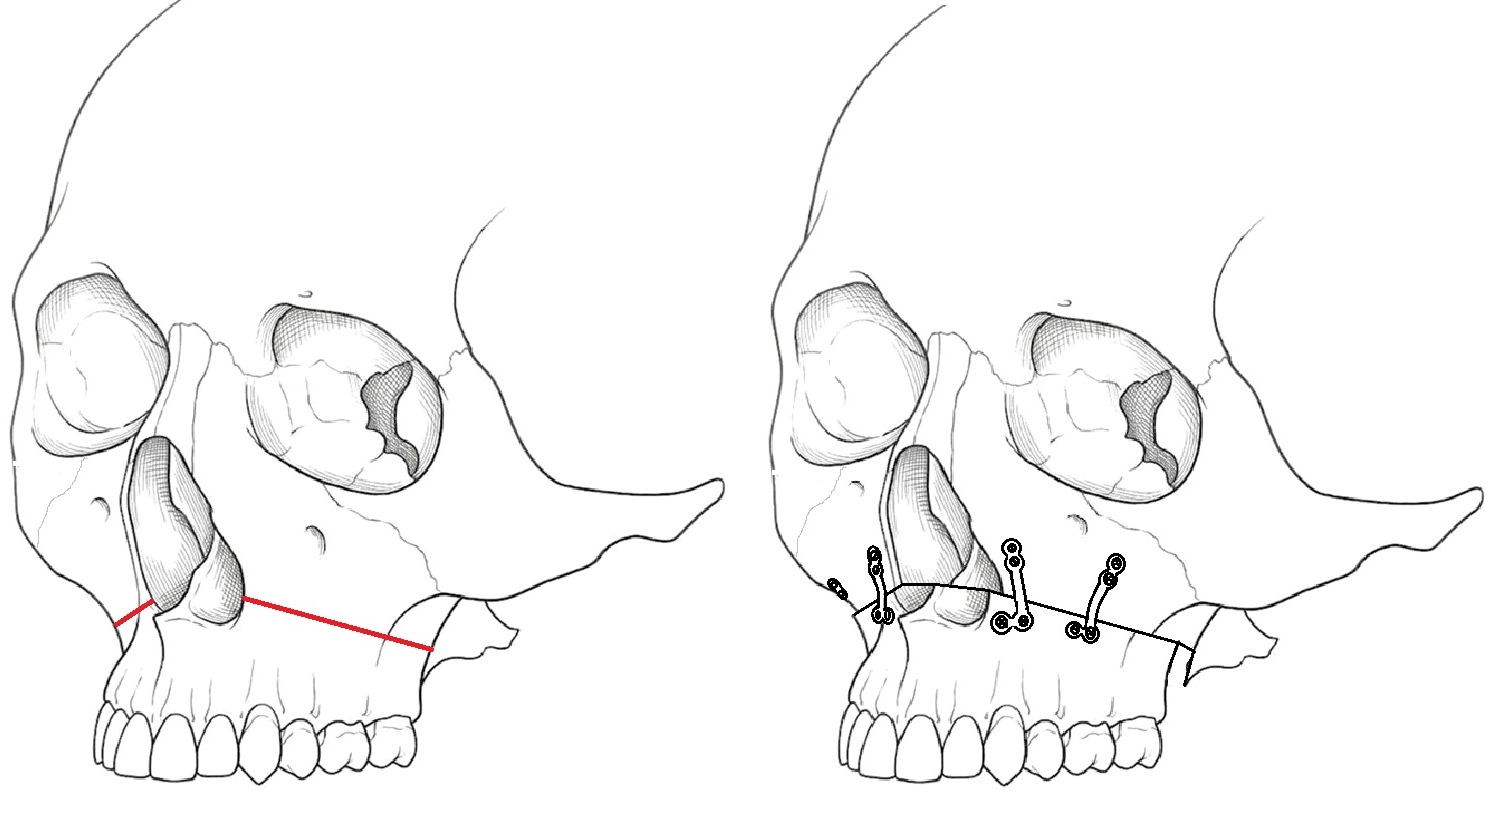

下顎枝矢状分割術

骨格性下顎前突症や小下顎症に対して、下顎枝矢状分割術が選択されます。下顎骨内には下歯槽神経(下顎の歯や歯肉、下唇、オトガイの知覚を司る)が走行しており、下顎枝矢状分割術は、比較的下歯槽神経を保護しながら手術ができます(患者様の解剖形態によります)。また、骨切断面の接触面積が大きいことから、骨癒合が得られやすいといったメリットがあります。また、移動量や移動方向の許容範囲が大きく、下顎左右非対称にも対応が可能です。

手術は全身麻酔下で行い、歯を含む下顎骨の一部を切って移動し、噛み合わせを整えます。移動後の骨は体に害のない材料でできたネジやプレートで固定します。

手術後は上下の噛み合わせを固定した状態で過ごしていただき、顎の安静を保ちます。手術はすべての操作を口腔内で行うことから、顔の皮膚に傷痕が残ることはありません。